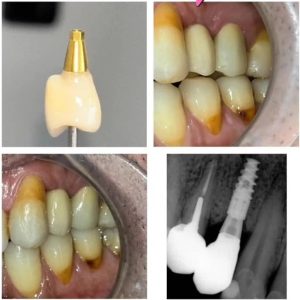

- Chirurgie implantaire et prothèse sur implant.

- Implantologie.